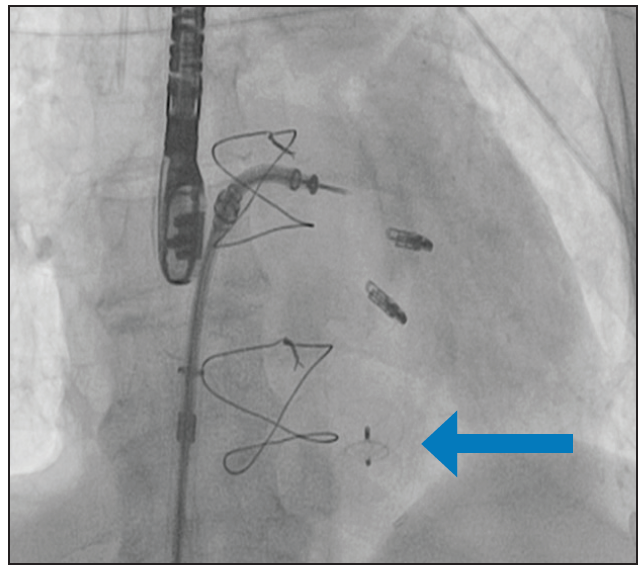

APPROACH OF THE MODERATOR

We performed transcatheter closure of the LV pseudoaneurysm with a 16-mm Amplatzer VSD occluder and transcatheter mitral valve repair with a MitraClip (Figure 1). The choice of this particular device and size were based on the CTA sizing. We inserted the deflectable 8.5-F Agilis sheath (Abbott) through the left brachial artery into the left ventricle (the length of the Agilis was too short for the femoral approach in this patient). We then inserted the 5-F pigtail catheter into the Agilis. The sheath was deflected to navigate toward the defect in left anterior oblique cranial projection. After we confirmed the tip of the pigtail was in the pseudoaneurysm, we proceeded with the closure. The deflectable sheath greatly improved the navigation. Because the severe mitral insufficiency persisted, we decided to perform the MitraClip procedure as a second stage. The procedure successfully reduced the regurgitation from severe to mild (Figure 2).

The patient was weaned from inotropes and IABP on postoperative day 2 and could ambulate on day 3. He was discharged to the cardiac rehabilitation unit on day 7 for 3 weeks. Most recently, at 1-year follow-up, the patient was New York Heart Association class II, with a 30% to 35% LVEF and mild MR. Placement of an implantable cardioverter defibrillator was considered, but the patient ultimately declined.